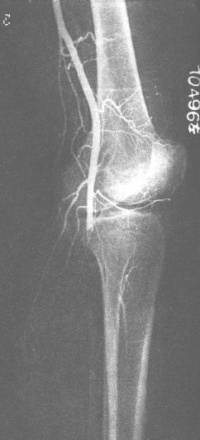

四肢动脉造影可显示动脉阻塞部位和侧支循环情况,可与闭塞性动脉硬化症的表现颇为相似。在血栓闭塞性脉管炎,动脉造影可发现管腔变狭小,至后期一段血管呈完全闭塞。在闭塞处之上管腔较光滑、无充盈残缺现象,其血管并不呈扭曲状。血栓闭塞住脉管炎与闭塞性动脉硬化症都可产生侧支循环,